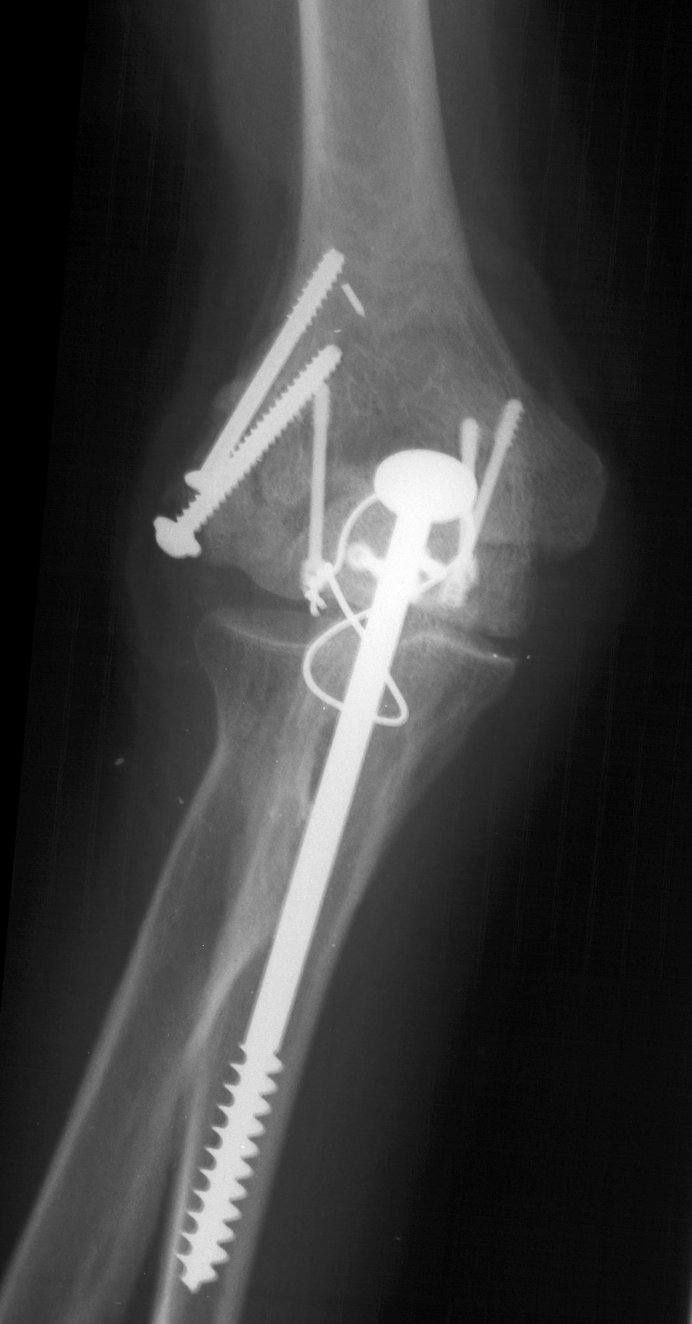

Clinical Example: Transcondylar distal humerus fracture repaired with Herbert screws

Transcondylar distal humerus fractures are usually high energy comminuted difficult fractures, technically difficult to manage. Anatomic reduction, rigid fixation and early motion are desirable, if technically possible. There are a variety of techniques for fixation. Here, Herbert screws were used to secure the two central purely osteochondral fracture fragments to each other and to the proximal humerus.

The olecranon osteotomy was closed with a 6.5 mm lag screw and (belt and suspenders) tension band technique.

Click for larger image

Anatomic reduction.

She began immediate protected motion and discontinued splint use at two weeks, despite recommendations to the contrary. These films are two months postop:

Lateral column not yet fully consolidated on Xray, but clinically healed.